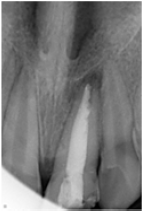

A 10 year old female patient complained of pain in upper front tooth region since one month. On taking detailed history it was revealed that the child had experienced dental trauma to anterior teeth six months back. Two days after the trauma they had availed dental services for the dental pain. However, the treatment was discontinued and follow up wasn't done by the guardians as the pain had subsided. After this anterior teeth remained asymptomatic until last month. History of present illness revealed that the nature of the pain was dull, constant, diffused with moderate severity which aggravated by intake of hot fluids. Intra-oral examination showed fracture involving the enamel in 11 and involving enamel, dentin and exposing pulp in 21. A large access opening was seen on the lingual side of11. On vertical percussion 21 was tender. Pulp vitality tests were done, which elicited negative responses in 21. Based on the above clinical signs and symptoms, a provisional diagnosis of complicated crown fracture leading to chronic apical periodontitis in 21 and uncomplicated crown fracture in 11 was proposed. Intra oral periapical radiograph revealed an incompletely formed apex with diffuse radiolucency (measuring 0.5x0.5cm) in greatest dimensions with respect to 21. It also showed radiopacity in 2/3rd of the canal of 21 which was indicative of intracanal medicament placed in the previous dental visit (Figure 1). Thus, a diagnosis of chronic periapical abscess in 21 was made. The treatment plan presented was to perform apexification in 21. Informed consent was taken by the guardians after explaining them the treatment planned in detail.

Figure 1: Periapical region of 21 showing open apex with radiolucency indicative of chronic apical periodontitis. The canal showed radiopacity in 2/3rd of the canal, indicating intra-canal dressing in the canal.